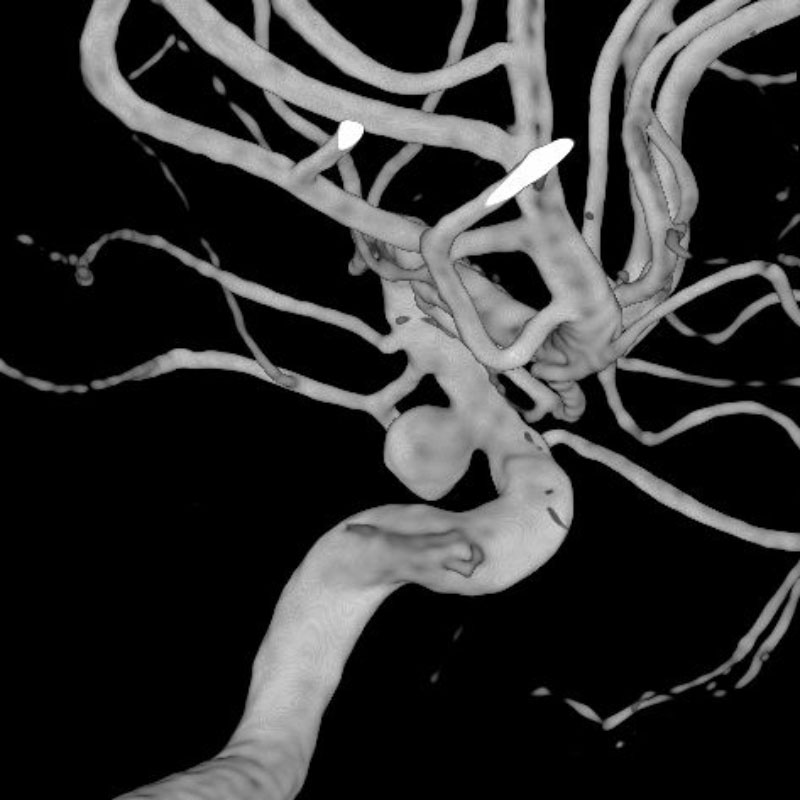

脳動静脈奇形

血管塞栓術

芝野/古谷